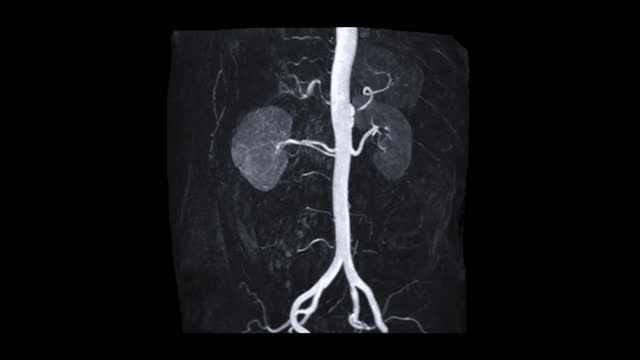

- 영상 검사를 통해 신장의 이상을 확인합니다. CT 스캔, MRI, 혹은 초음파 등의 영상검사를 통해 신장암의 덩어리를 확인할 수 있습니다.